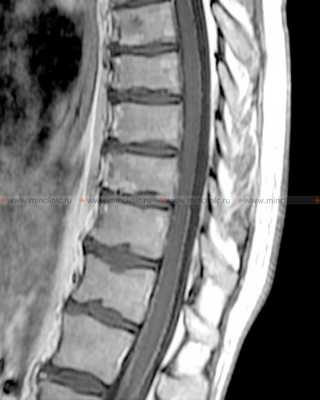

Больной находится в положении лежа на боку с согнутыми в тазобедренных и коленных суставах ногами, приведенными к животу; шея слегка согнута. Обычно люмбальную пункцию производят в промежутках между остистыми отростками L3-L4 или L4-L5. Ориентируются при этом на остистый отросток L4, который располагается на середине линии, соединяющей вершины гребней подвздошных костей.

Люмбальную пункцию (ЛП) производят в промежутках между остистыми отростками L3-L4 или L4-L5 позвонков.

На МРТ спинного мозга после контрастирования визуализируется так называемая "сахарная глазурь" у пациентов с лептоменингеальными метастазами при канцероматозе оболочек мозга.